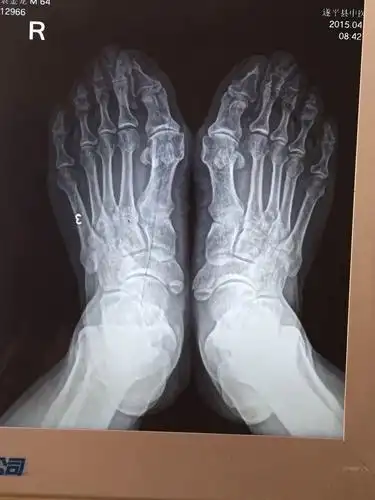

18岁女孩和妈妈都是大脚骨,是遗传吗,怎么治?骨科老牛来支招!

大脚骨病的微创手术

俗称"大脚骨",现行右足矫形,软组织,籽骨松解复位 chevron截骨 关节囊

拇外翻大脚骨

拇外翻大脚骨手术矫治术